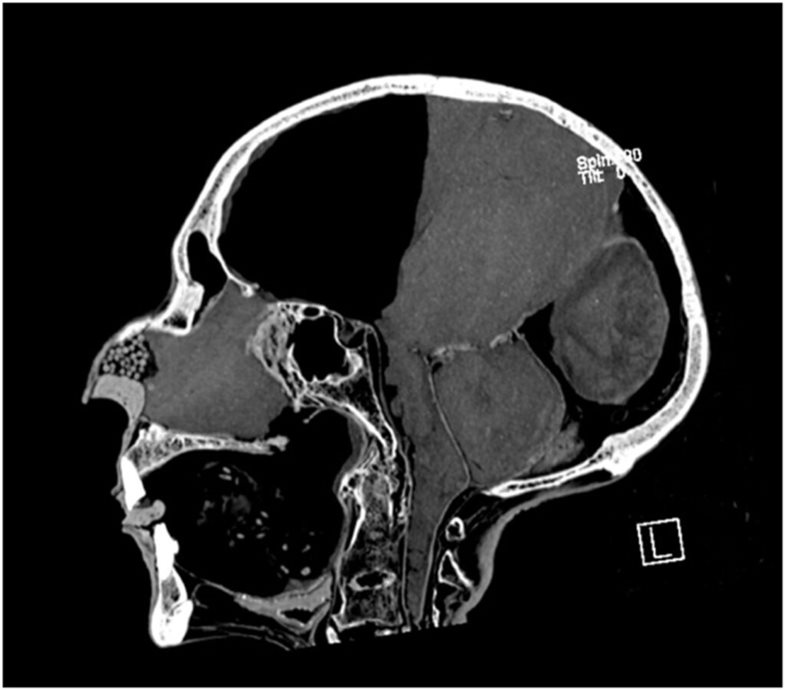

Zweidimensionales CT-Bild des Kopfes von Ramses II. Die Einbalsamierern legten einen kleinen Tierknochen und schwarze Pfeffersamen in die Nasenhöhle, um die Form der Nase zu erhalten

Zweidimensionales CT-Bild des Kopfes von Ramses II. Die Einbalsamierern legten einen kleinen Tierknochen und schwarze Pfeffersamen in die Nasenhöhle, um die Form der Nase zu erhalten © Sahar Saleem.